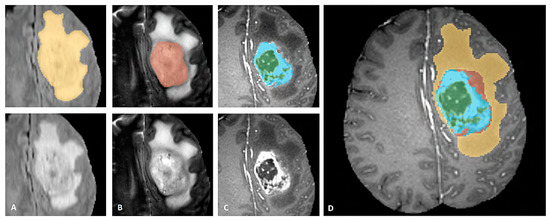

BraTS dataset provides annotations for the training cases with four different classes (Necrosis, Edema, Enhancing, and Non-Enhancing) and the fifth class is considered as everything else. The dataset is also described in three sub-compartment regions. Region 1 is known as Complete Tumor with labels 1, 2, 3, 4 in the annotated data. Region 2 is known as Tumor Core with labels 1, 3, 4, and Region 3 which is known as Enhancing Tumor with label 4 in the annotated data. The description of data labeling is presented in Table 3 and Figure 7 shows a sample of the labeled multiclass tumor in MR image. In Figure 7, the yellow color represents the whole tumor, red represents the core tumor, light blue represents enhancing tumor and green patches show the necrotic core [22].

Figure 7. Sample of Multiclass Glioma labels with different modalities. The image label shows: (A). Whole tumor, (B). Tumor core, (C). Enhancing Tumor and (D). Combined all tumor types [22].